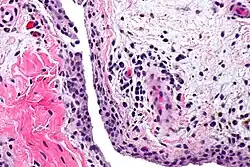

![]() Акварельный рисунок острого синовита коленного сустава, показывающий начало распада хряща внутреннего мыщелка. | |

Синови́т, лат. synovitis (от лат. (membrana) synovialis — синовиальная оболочка и суффикса -itis, обозначающего воспалительный процесс) — воспаление синовиальной оболочки, ограниченное её пределами и характеризующееся скоплением выпота в выстилаемой ею полости (в синовиальной сумке, влагалище сухожилий, суставной полости)[1][2].